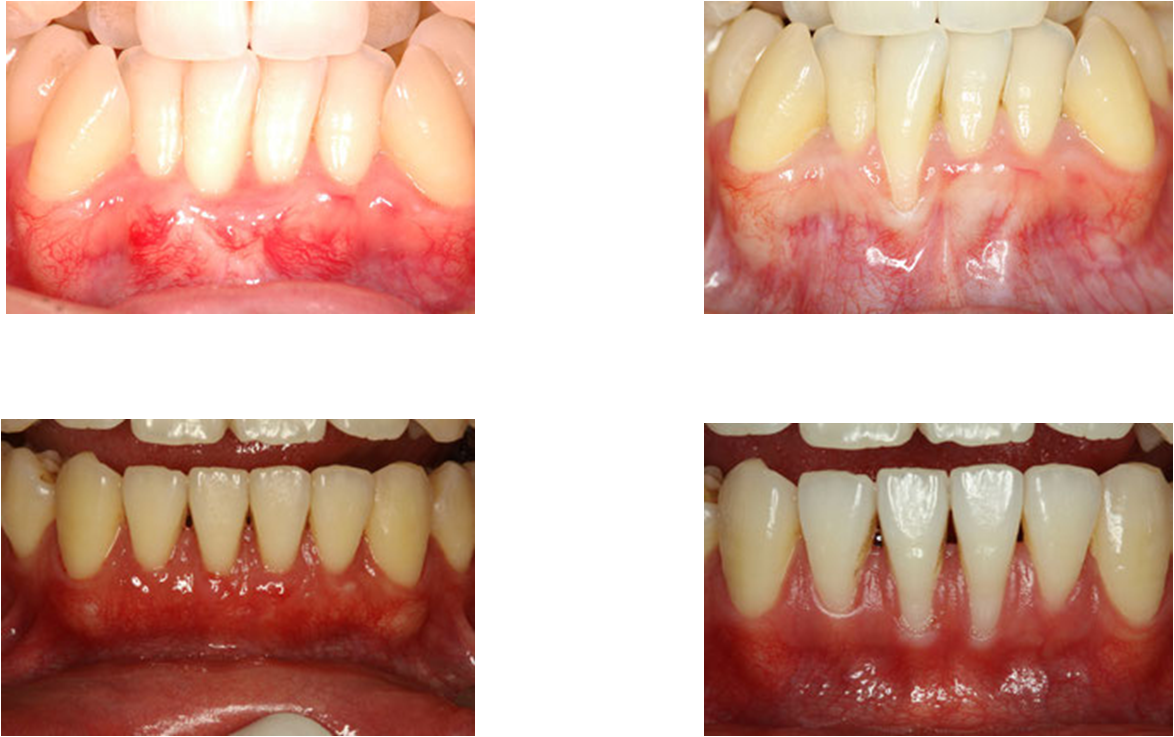

上の画像を診てもらうと分かると思うのですが、歯茎がはれてところどころ出血もあります。

結果として、以下のような方も、歯茎を減らすことなく、しっかりと治療することができるようになりました。